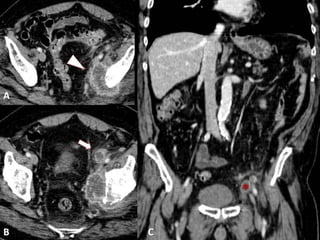

• #17 METASTASIS GANGLIONAR DE CARCINOMA UROTELIAL. A) Imagen axial de TCMD que muestra importante componente adenopático ilíaco izquierdo con centro de aspecto necrótico y periferia hipervascular afectando parcialmente hueso ilíaco homolateral (punta de flecha en A). B) Adenopatía inguinal izquierda de similares características siendo todas ellas compatibles con afectación metastásica. C) Reconstrucción multiplanar coronal. Adenopatía inguinal izquierda referida previamente (asterisco).

• #18 CARCINOMA ESCAMOSO. Imágenes axiales por TCMD en fase nefrográfica (A) y en dase excretora (B) que muestran engrosamiento mural de pared antero-lateral derecha de vejiga urinaria que se realza tras la administración de contraste y presenta crecimiento endoluminal. Se observan signos que sugieren infiltración de la grasa perivesical adyacente a la pared lateral derecha de la vejiga (punta de flecha).